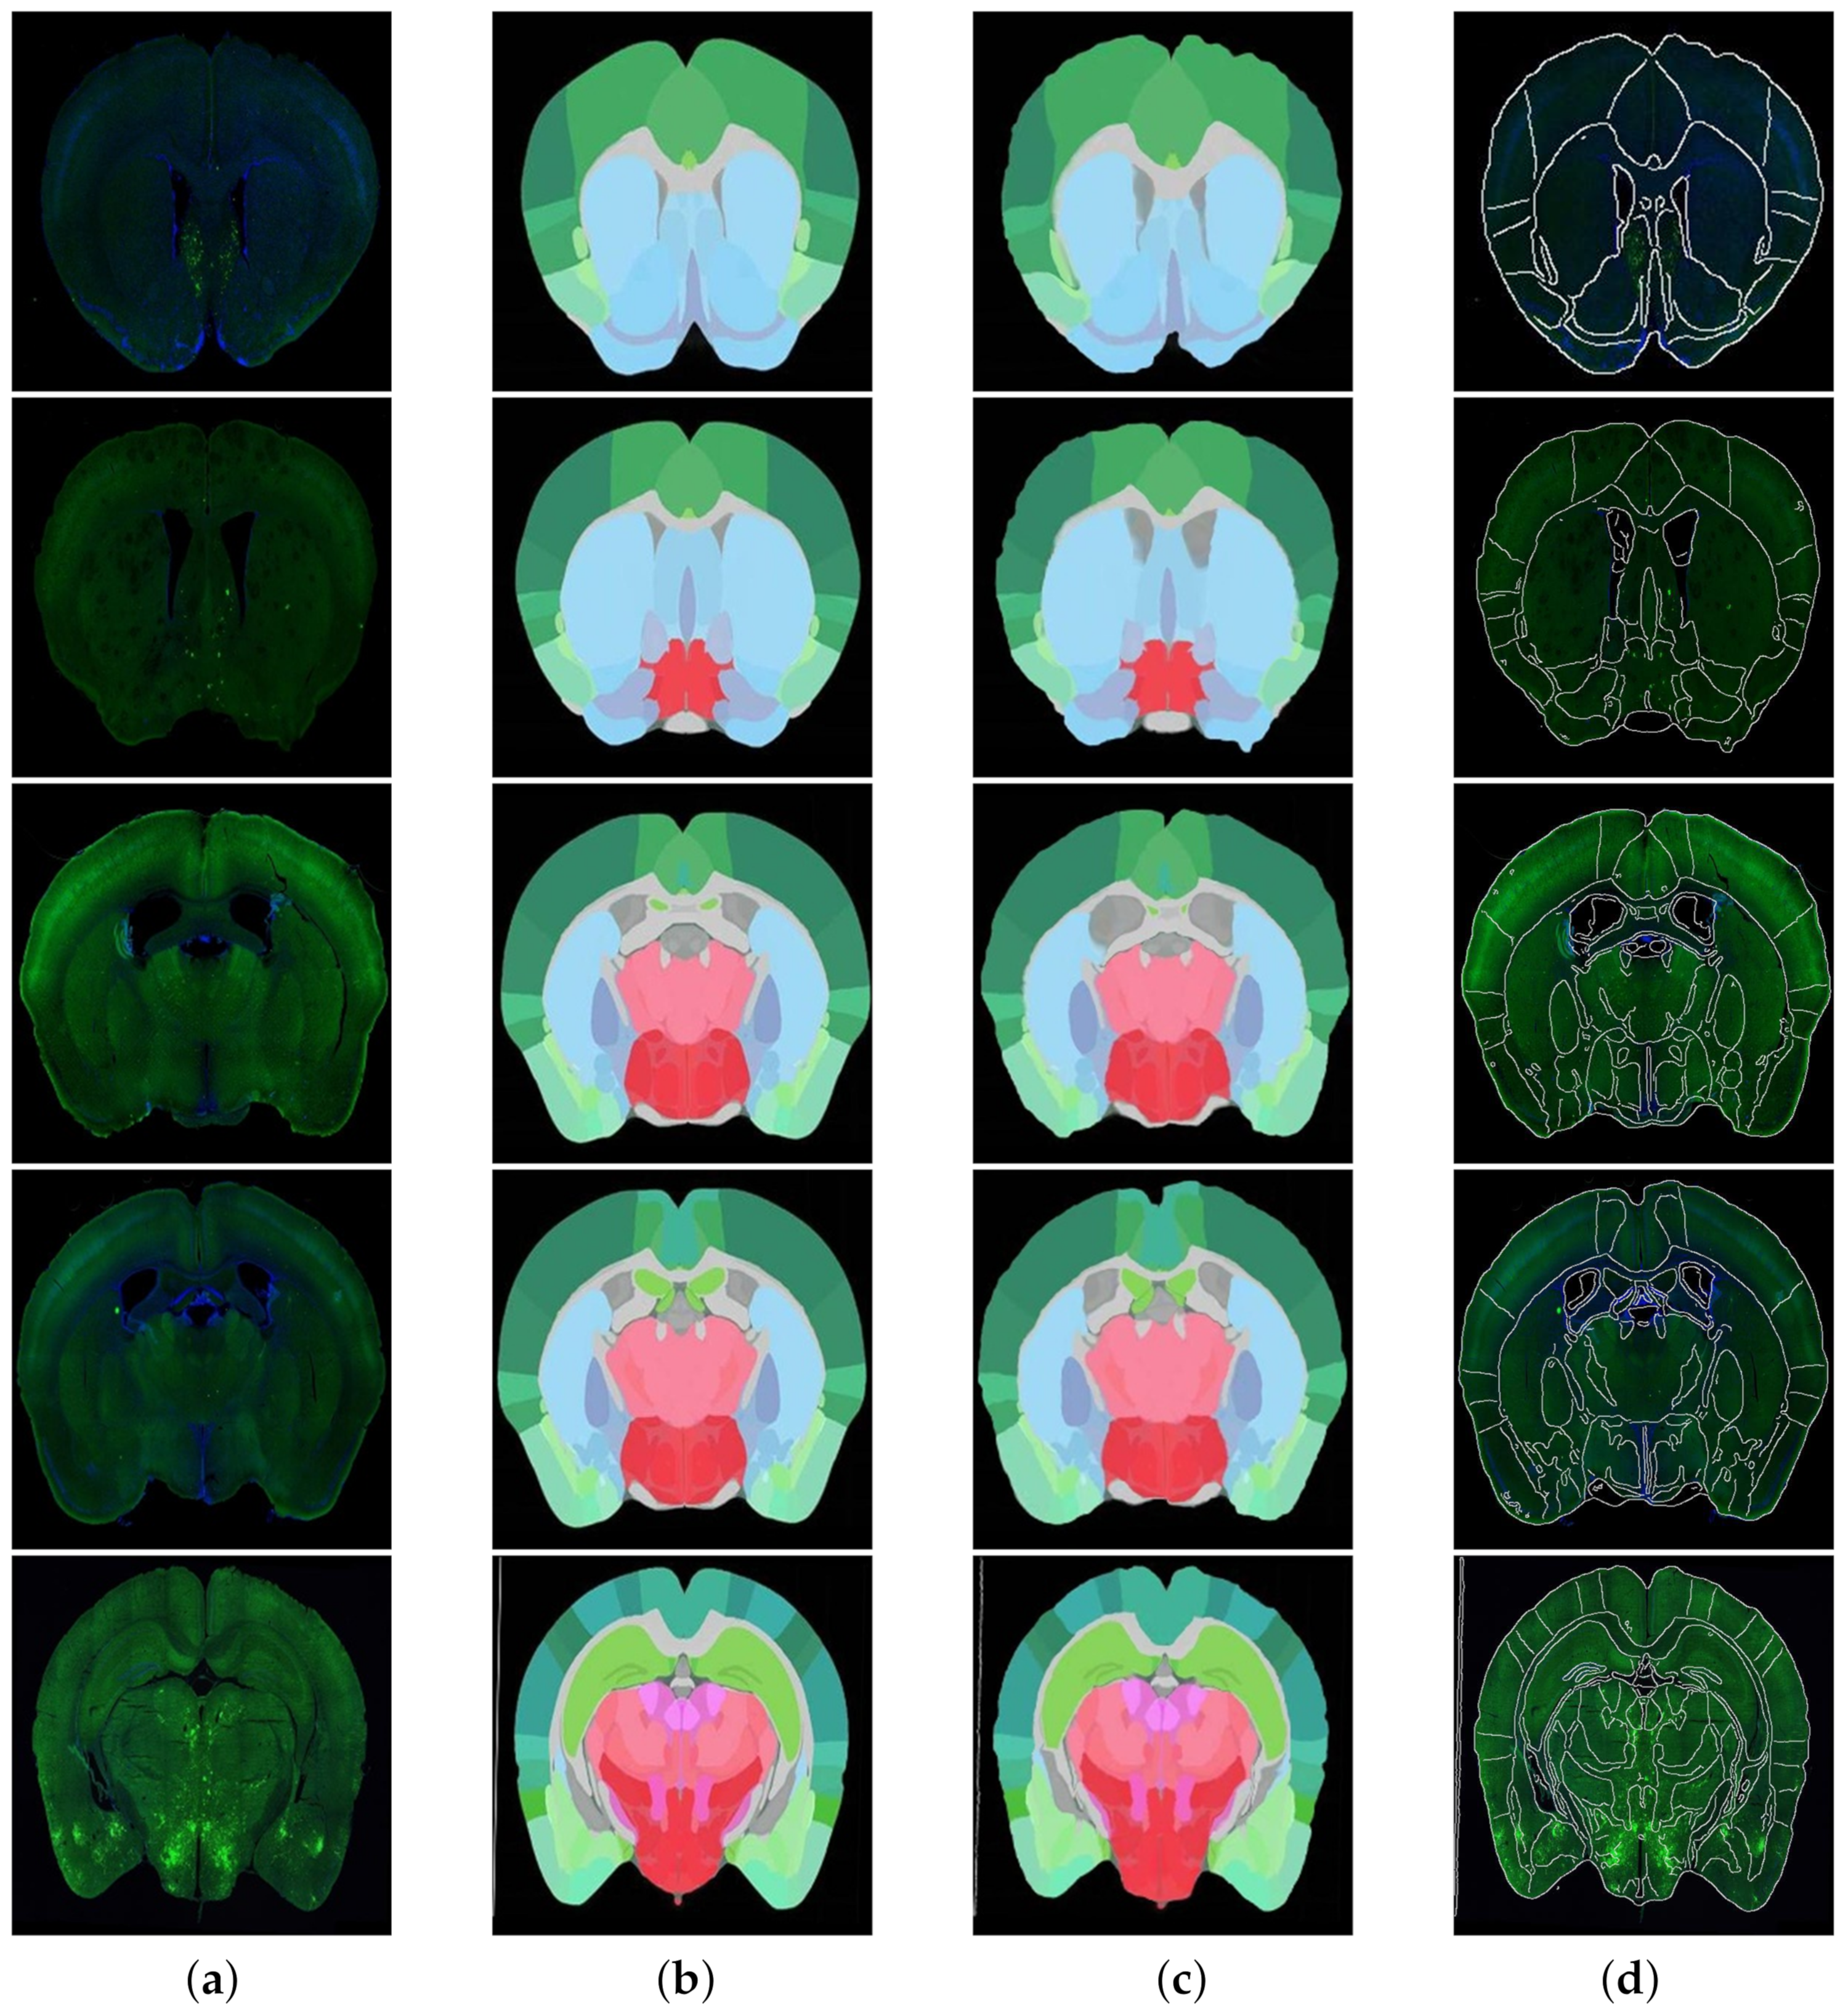

To better solve the problem of non-unified multi-modal image registration, using the modal transformation method to convert a multi-modal image into a monomodal image is an effective method. In this study, a Joint Enhancement of Multimodal Information image segmentation method was proposed. It segments the corresponding key features in the image to complete the modal transformation. To verify the performance of the proposed method, the U-Net network suitable for small samples was selected for comparison, and the results are shown in Figure 7. The commonly used evaluation indicators of PA, MPA, MIOU and FWIOU for image segmentation were used. The results were evaluated, and the performance analysis is shown in Figure 8.

The experimental results indicate that the U-Net network can accurately segment the ATA images with obvious features and less noise. As for some brain slice images with no obvious features and a lot of noise, they could not recognize the key features or achieve satisfactory segmentation results. The JEMI network proposed in this study trains two multi-modal images together, and, by fusing the input multi-modal information, it can both promote and enhance the learning of key features and also restrict the influence of marker neurons to achieve a better effect of modal transformation ultimately.

Figure 7. Results for Brain Slices and ATA using different modal transformation methods; the original Brain Atlas and original brain slices (middle); the effect of using the U-net method for modal transformation (left); the effect of using the JEMI method for modal transformation (right). It was obvious by comparison that the JEMI method was better.